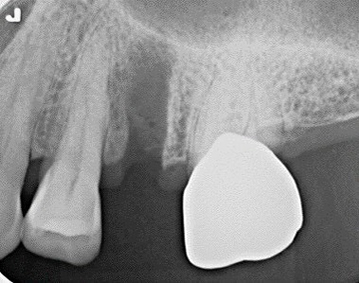

Before術前

After術後